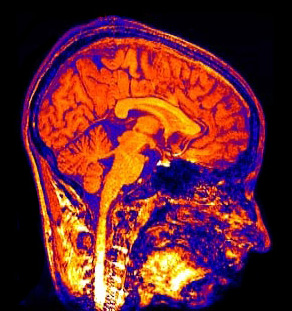

Таня Сингер (Tania Singer) из Университетского колледжа в Лондоне и ее коллеги для исследования этих тонких материй воспользовались методом магнитно-резонансной томографии (МРТ). В отличие от обычной электроэнцефалографии, которая регистрирует реакцию относительно больших участков мозга, эта передовая методика позволяет отслеживать возбуждение групп нейронов и даже отдельных нейронов. МРТ фиксирует портрет мозга непосредственно в момент ответа на сигнал извне. Лондонских нейрофизиологов интересовал процесс появления в мозге реакции сопереживания боли, а также появляется ли реакция сопереживания к людям с социальным и асоциальным поведением. Критерием социальности считали в эксперименте способность к кооперации, корпоративную честность. В действительности за сложными и скрупулезно точными формулировками ученых стоит простой человеческий вопрос: может ли человек, зарекомендовавший себя как эгоист и мошенник, рассчитывать на простое человеческое сочувствие?

На втором этапе экспериментов испытуемому показывали косвенными сигналами, что честный и нечестный игроки переживают боль. Во время демонстрации сигналов у испытуемого снимали томограмму мозга. Что же выяснилось? Честному игроку сочувствовали все: и мужчины, и женщины. Иначе говоря, в ответ на косвенный сигнал о переживании боли честным игроком в центрах боли у испытуемых фиксировалось специфическое болевое возбуждение.

А как же мошенники? Почти все испытуемые женщины сопереживали нечестным игрокам так же, как и честным. А вот мужчины — нет. Сигнал о переживании боли нечестным игроком не вызывал у них никакого сочувствия! Мало того: вместо болевых центров у большинства мужчин-испытуемых возбуждался особый центр «награды». Зная, что игрок-мошенник испытывает боль, мужчины в большинстве испытывали буквально злорадство, или законное чувство мести и справедливости. У женщин злорадство фиксировалось редко.